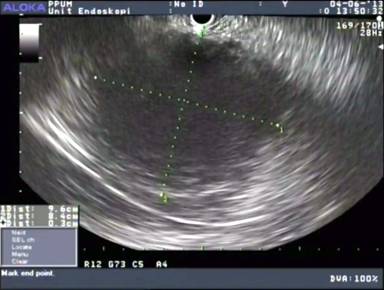

The procedure was done under midazolam infusion by an anesthetist. EUS was performed with a curved linear array echoendoscope (GF-UCT 180 Olympus America Inc., Centre Valley, PA, USA) and Aloka 5 system (Olympus America Inc., Centre Valley, PA, USA). A large, clear and non-septated cystic lesion measuring 9.7x10.0 cm arising from the pancreatic tail was identified. There was no obvious connection to the main pancreatic duct or features suggestive of chronic pancreatitis (Figure 2). The lesion was free form vascular invasion and no peri-lesional lymph nodes were seen. The lesion was punctured with a 19 gauge EUS fine needle aspiration (EUS-FNA) needle (Echo-tipTM, Wilson-Cook, Winston-Salem, NC, USA) and a 0.035” ZebraTM guide wire (Wilson-Cook, Winston-Salem, NC, USA) was inserted into the lesion forming a few loops within it. The aspirate was sent for CEA, CA19-9, amylase and cytology. The cystogastrotomy tract was formed using an 8.5-Fr Cystotome (Cook Endoscopy, Winston-Salem, NC) and a CRETM (Boston Scientific, Natick, MA, USA) wire guided balloon dilatation was done up to 8 mm. A novel lumen opposing CSEMS, Niti-STM Biliary Stent (NAGITM) (Taewoong-Medical Co, Seoul, South Korea) measuring 14 mm in diameter x 30mm in length was deployed into the tract successfully (Figure 3). A nasogastric tube was placed in the gastric cavity after the cystogastrostomy to prevent aspiration of large amounts of drained mucinous fluid.

Figure 2. Large, non-septated clear cyst in the tail of pancreas. |